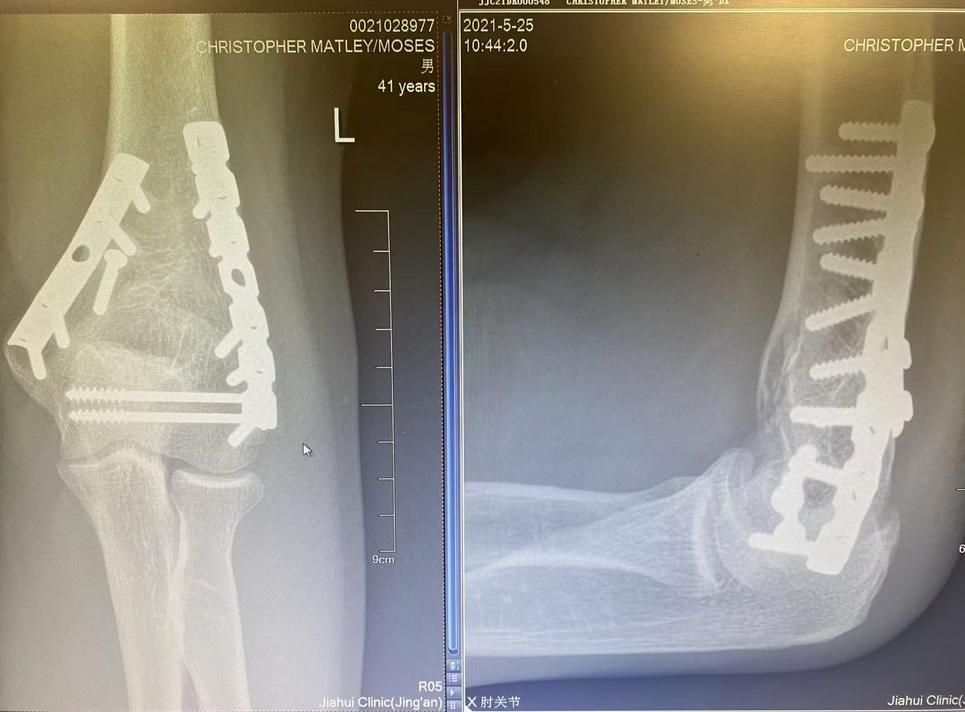

Next, I found myself under the glaring lights of The Miriam emergency room, where lights glared in the way only emergency room lights can glare. To confirm my mother’s incredible foresight, an orthopedic surgeon with a specialty in elbows happened to be in the hospital, and he tended to my care.

The left sleave of my shirt must have been cut off at some point, and he examined my wound. He held my arm ever so gently. He quickly determined that it couldn’t bend, it couldn’t move at all. He must have known, from experience, the extraordinary pain that even the slightest touch might cause. Yet, he said, I need to determine if you’ve had a compound fracture, if the bone pierced the skin. I didn’t know what that meant.

Could I have some Tylenol, I begged, could I have anything for the pain?

No, he replied, as kindly as he could: you might need surgery, and soon, and you can’t have anything in your stomach.

Worse, I need to determine if you’ve had a compound fracture.

This, as it happens, meant using a blunt, sterile medal tool to probe that ever-so-small slit on my elbow, to see if the probe would reach my bone, confirming that it had passed through the skin.

I felt pain beyond what I imagined pain could feel like. More than thirty years later, I cannot fathom that pain.

Again, shock. In an operating room, an anesthesiologist asked me to count down from ten. I think I got to eight.

Then I awoke and I saw my mom and dad and they cried. I remember I tried to pull the IV out of my arm, I tried to pull out this odd drain that wound under this huge, heavy plaster cast on my left arm: they felt itchy. No, no, no, you can’t. Then I went back to sleep.

Fourteen days after I shattered my elbow, on the morning of the 19th of October, a week after I had left the hospital, my father took me to see the orthopedic surgeon who had, miraculously, screwed and plated my elbow back into something that might eventually bend and twist like an elbow. Ever so gently, he removed the hulking plaster cast; ever so gently he held my arm for X-rays: I still remember how he suited up in a led vest, in a lead collar, because he knew he had to hold my arm just so, to position the X-ray plate just so, to avoid causing excruciating pain while still getting the films he needed. I remember that kindness, just as I remember his self-satisfaction at the sight of his handiwork revealed by radiation passed through: everything remained where it ought to be, and he could tell with a surgeon’s eye that my arm could again function normally, if after a tremendous amount of physical therapy. He removed the surgical staples that had been stapled into my arm at the end of my surgery. I remember how he showed me the way the tool worked, saying there wouldn’t be too much pressure, there wouldn’t be too much pain. Nothing more than the slightest pinch, and one by one those staples clinked into a metal tray. I got a new, lighter, cast, and I went home. I think I even went to school that afternoon. My dad went off to work.

I’m not sure if any of my classmates ever knew where I went for those couple of weeks, but I know all of them were kind enough not to ask or to even mention it. As the days grew longer and warmer, I really did start to feel better, and to see some hope in life. I could bend and rotate my elbow again, and I could carry my own bag. Through all of that excruciating physical therapy, I had regained nearly 90% of the original motion I had possessed, and hardly anyone would even be able to guess I had sustained such an injury. To this day my right arm, my already dominant arm, remains significantly stronger, and some things, like pull-ups, or rock climbing, or using an oar to paddle, still lead me to confront physical limitations. I have some slight nerve damage which means the two smallest fingers on my left hand don’t quite grasp as they might, don’t have the same dexterity they once did. But most every day and for most every task I want to complete, I have no problems. I have learned, though, about scars, and about things people carry on the inside, and how it shapes their lives in ways we might never see, no less comprehend. I learned about imbalance and how the slightest variations can cause enduring stress.